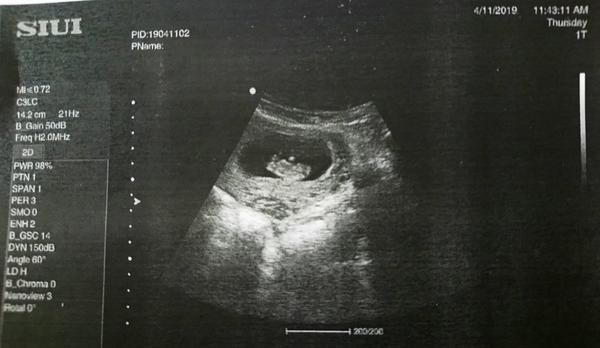

Tak... Dnesna kontrola ok ;) babatko zodpoveda tyzdnu, uz potvrdil akciu srdca na 100%... Dalsia kontrola o 3 tt... Knizku mi este nedal...

@hennyinnsbruck vies som zmatena z tych cisel... Podla ms 9+3, vak ma velkost 12+1 a do spravy napisal velkost plodu 8+2 a ustne povrdal ze to vidi na 8-9tt no a potom nebud z toho kus nervozna...

...... Co sa týka plodu + - týždeň je nic

Co sa týka vaku to nemám šajnu, ale keby niečo nebolo ok lekár by iste povedal 😉😉 takže kľud a užívaj si tehotenstvo 😊😊